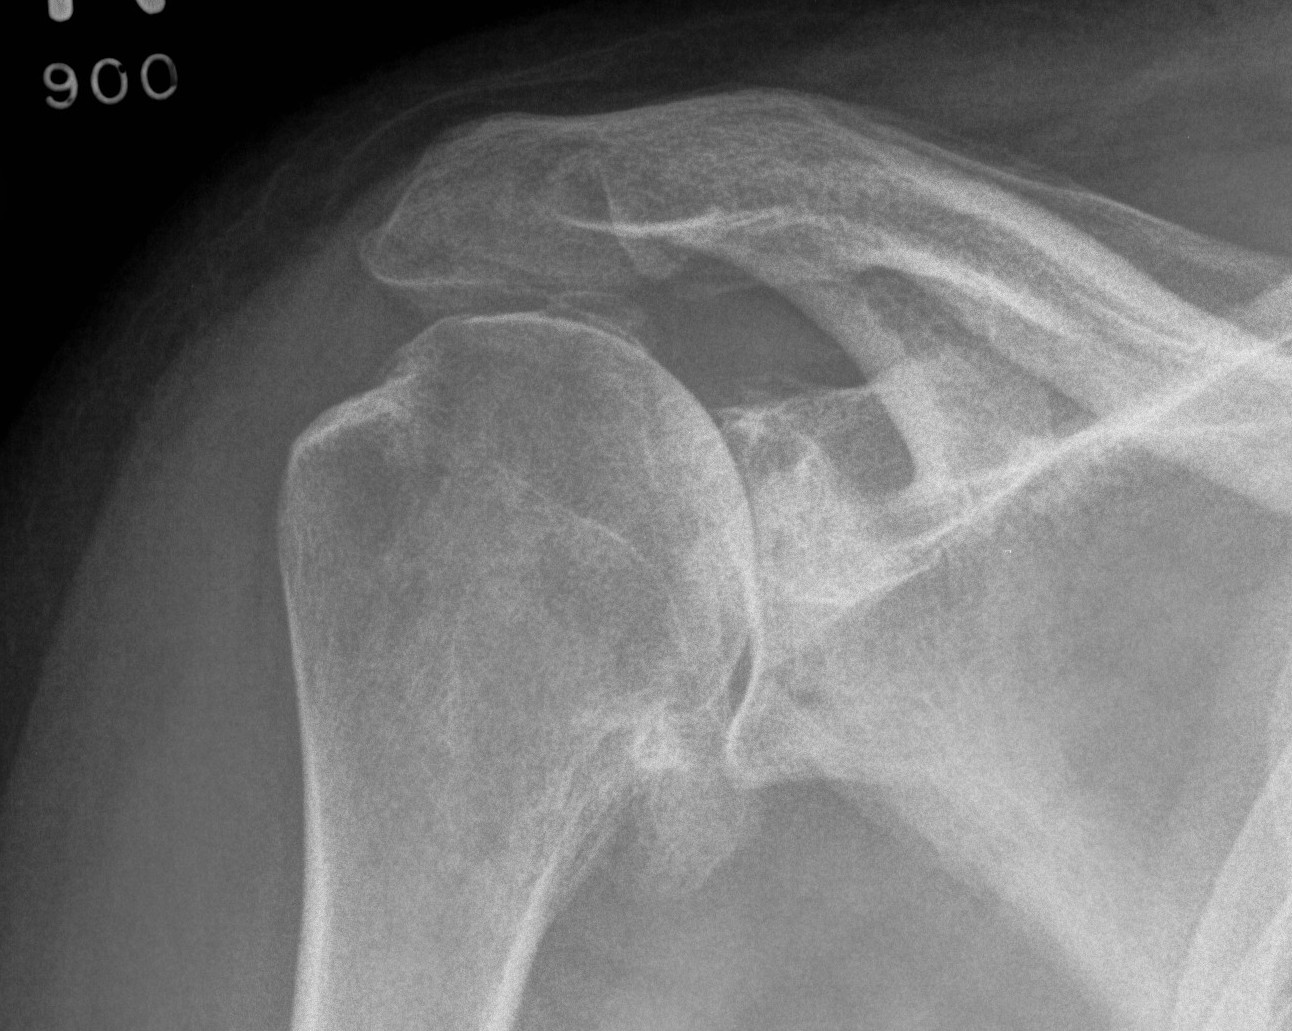

X-ray

Typical changes of OA

1. Teardrop / beard osteophytes on inferior head & glenoid

2. Osteochondral loose bodies

Beard osteophytes

Osteochondral loose body